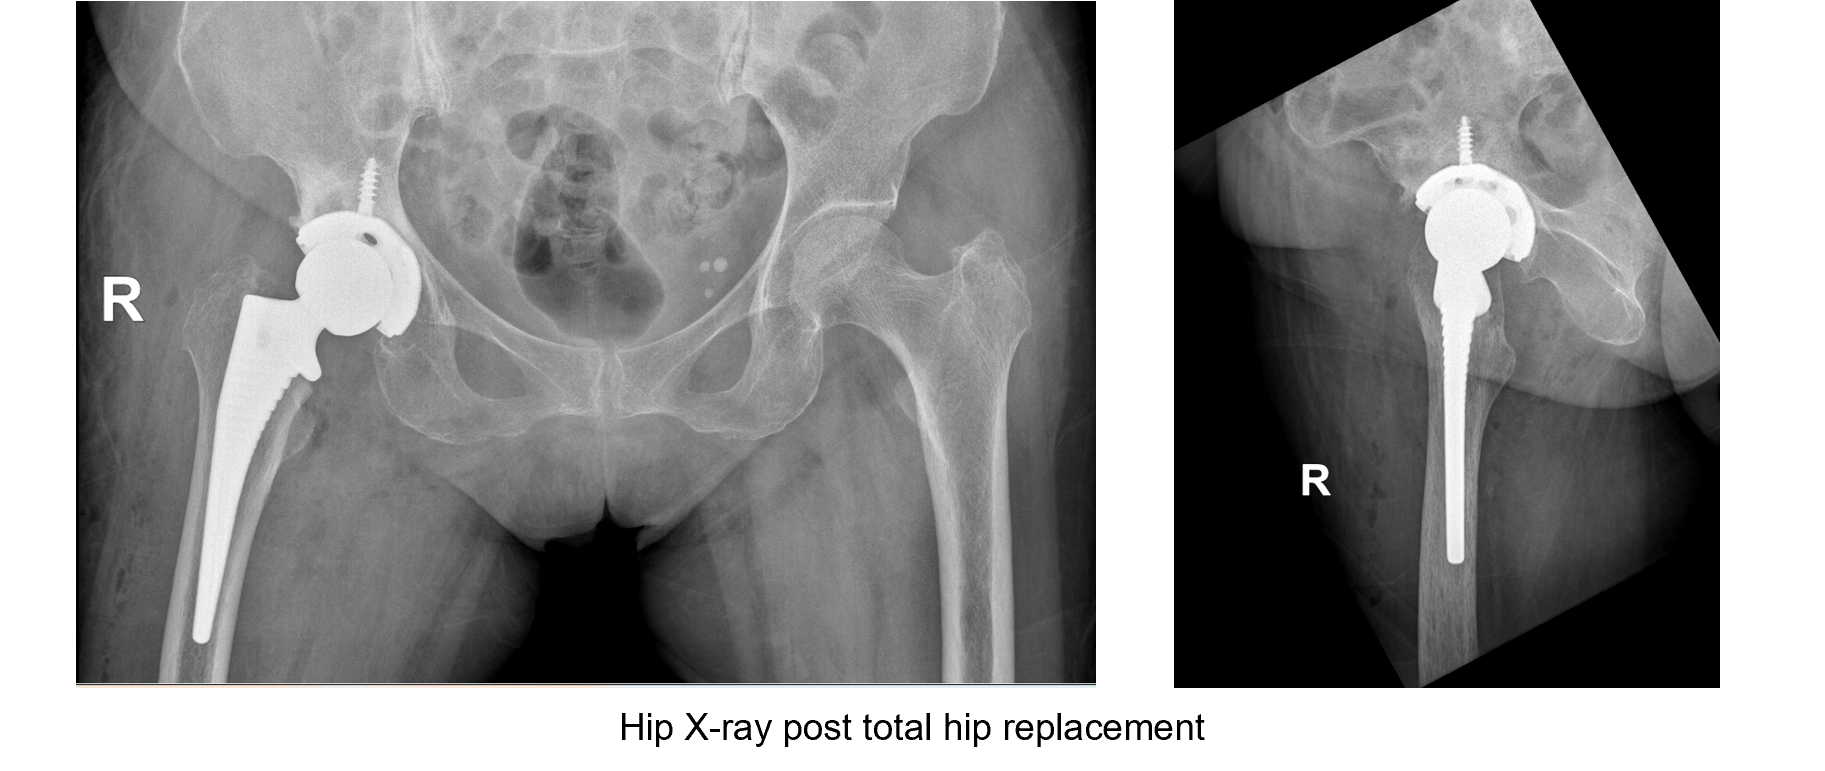

Surgical

- Right total hip replacement

After 3 months of subcutaneous Romosozumab and correction of the vitamin D levels with cholecalciferol treatment, patient opted for total hip replacement.

Intraoperatively, the bone was noted to be fragile. Extra care was carried out to avoid intraoperative iatrogenic fracture. The surgery was performed uneventfully.